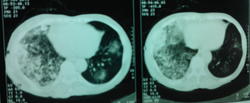

Случай достаточно непростой. Сразу обратил внимание на выраженую компенсаторную эмфизему левого легкого. Правое значит очень плохо функционирует. И причиной этого может быть и обширность поражения, и бронхообструкция, и то и другое вместе. Полости могут быть и при туберкулёзе, и при абсцедирующей прневмонии, и при раке с распадом. Абсцесс вроде бы не вписывается в лабораторные показатели, но у хронических алкоголиков может быть убитый иммунитет. Туберкулез, на мой взгляд, при такой обширности, должен был дать отсев и в другое легкое. Так что, из этих рассуждений больше склоняюсь к раку. В таком неоднозначном случае всеравно следует оставить диф. ряд: рак, тбц, абсцедирующая пневмония и уговорить пациента на КТ, бронхоскопию.

По-моему это типичная картина активного туберкулеза - инфильтраты со склонностью к слиянию, очаги с нечеткими контурами.. Средостение смещено вправо, что может указывать на фиброз в правом легком.. Спокойные анализы, неяркая клиника туда же - к туберкулезу. На каком основании фтизиатр так быстро сказал, что это не его?

Никак нельзя исключить казеозную пневмонию правого легкого с отсевами в нижнюю долю левого легкого . Нужны снимки в динамике. (бывший фтизиатр, в настоящем- рентгенолог). В мокроте КУМ не сразу может выделить.

+1. А слева отсевы в язычки.

С отсевом в "язычки" слева, как по мне, тоже не поспоришь.

провели кт: заключение по КТ ОГК - картина деструктивной полисегментарной пневмонии правого легкого, и сегментарной нижней доли левого, КТ ОБП - картина жировой дистрофии печени, киста левой почки. Сами снимки мне увидеть не удалось - родственники зачем то увезли в деревню, надеюсь привезут на днях и я хотя бы их сфотографирую для вас.